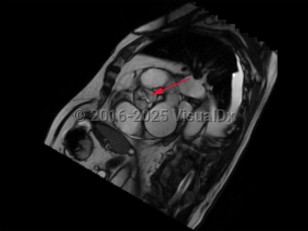

Aortic stenosis

Aortic stenosis (AS) is the narrowing of left ventricular outflow through the aortic valve. It is the most prevalent cause of ventricular outflow obstruction, and it is increasing in prevalence as the population ages and life expectancy increases. While patients are generally asymptomatic in the presence of mild outflow obstruction, exertional dyspnea, chest discomfort, fatigue, dizziness, and syncope develop as the degree of obstruction progresses.

Contributing etiologies include calcification of the aortic valve cusps (most common in the elderly population), congenital abnormalities (ie, bicuspid aortic valve), rheumatic fever, chest radiotherapy, endocarditis, and alkaptonuria. Potential complications include heart failure, cardiac arrhythmias, infectious endocarditis, pulmonary hypertension, excessive bleeding, stroke, and other embolic events.